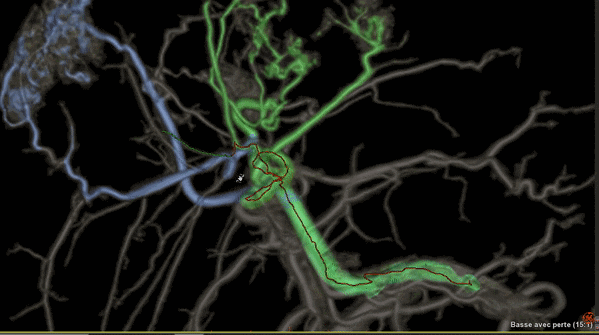

Liver ASSIST V.I,一種增強型軟件

可利用分析工具幫助臨床醫(yī)生克服腫瘤治療的挑戰(zhàn),例如,阻斷肝部腫瘤周邊供養(yǎng)血管是一種有效的介入治療方法,Liver ASSIST V.I可以通過精確高效的血管解剖分析來界定并精準選擇注射點,如同Google地圖一樣進行路徑引導,可以術前進行手術預演來提供手術的精準度,減少手術并發(fā)癥,讓人工智能的智慧在介入治療中閃光。